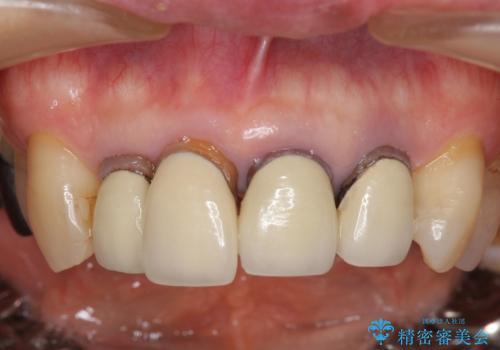

老朽化した前歯のセラミック治療やりかえ

- 20年前に治療した前歯のセラミッククラウンが老朽化し見た目の改善を求めて来院されました。

クラウン治療は経年的に歯ぐきの位置が変わり汚れが溜まってしまったり、見た目が悪くなるなどの問題が出てくることがあります。